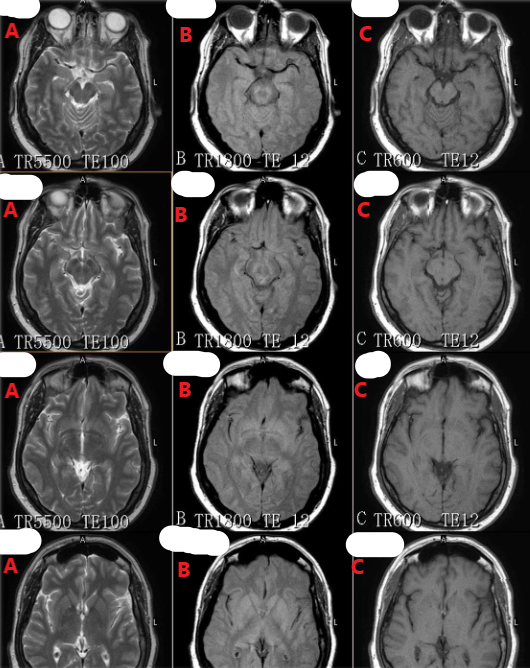

Which row of these images are T2 weighted ?

A

Which row of these images are T1 weighted ?

C

Which row of these images is T2 weighted with fat signal suppressed ?

D

When imaging a hemorrhagic infarct in the brain, which pulse sequence would demonstrate the magnetic susceptibility effects better?

C and/or D